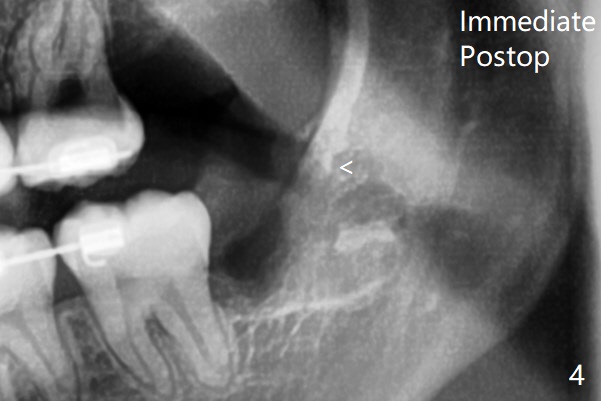

14岁外斜嵴尚未完全形成(图一:箭头);17岁时外斜嵴近中部分仍然被智齿阻挡而没有形成或者去除颊侧骨板时失去(图四),但是密度增加。这两个智齿不位于第二磨牙颊侧。